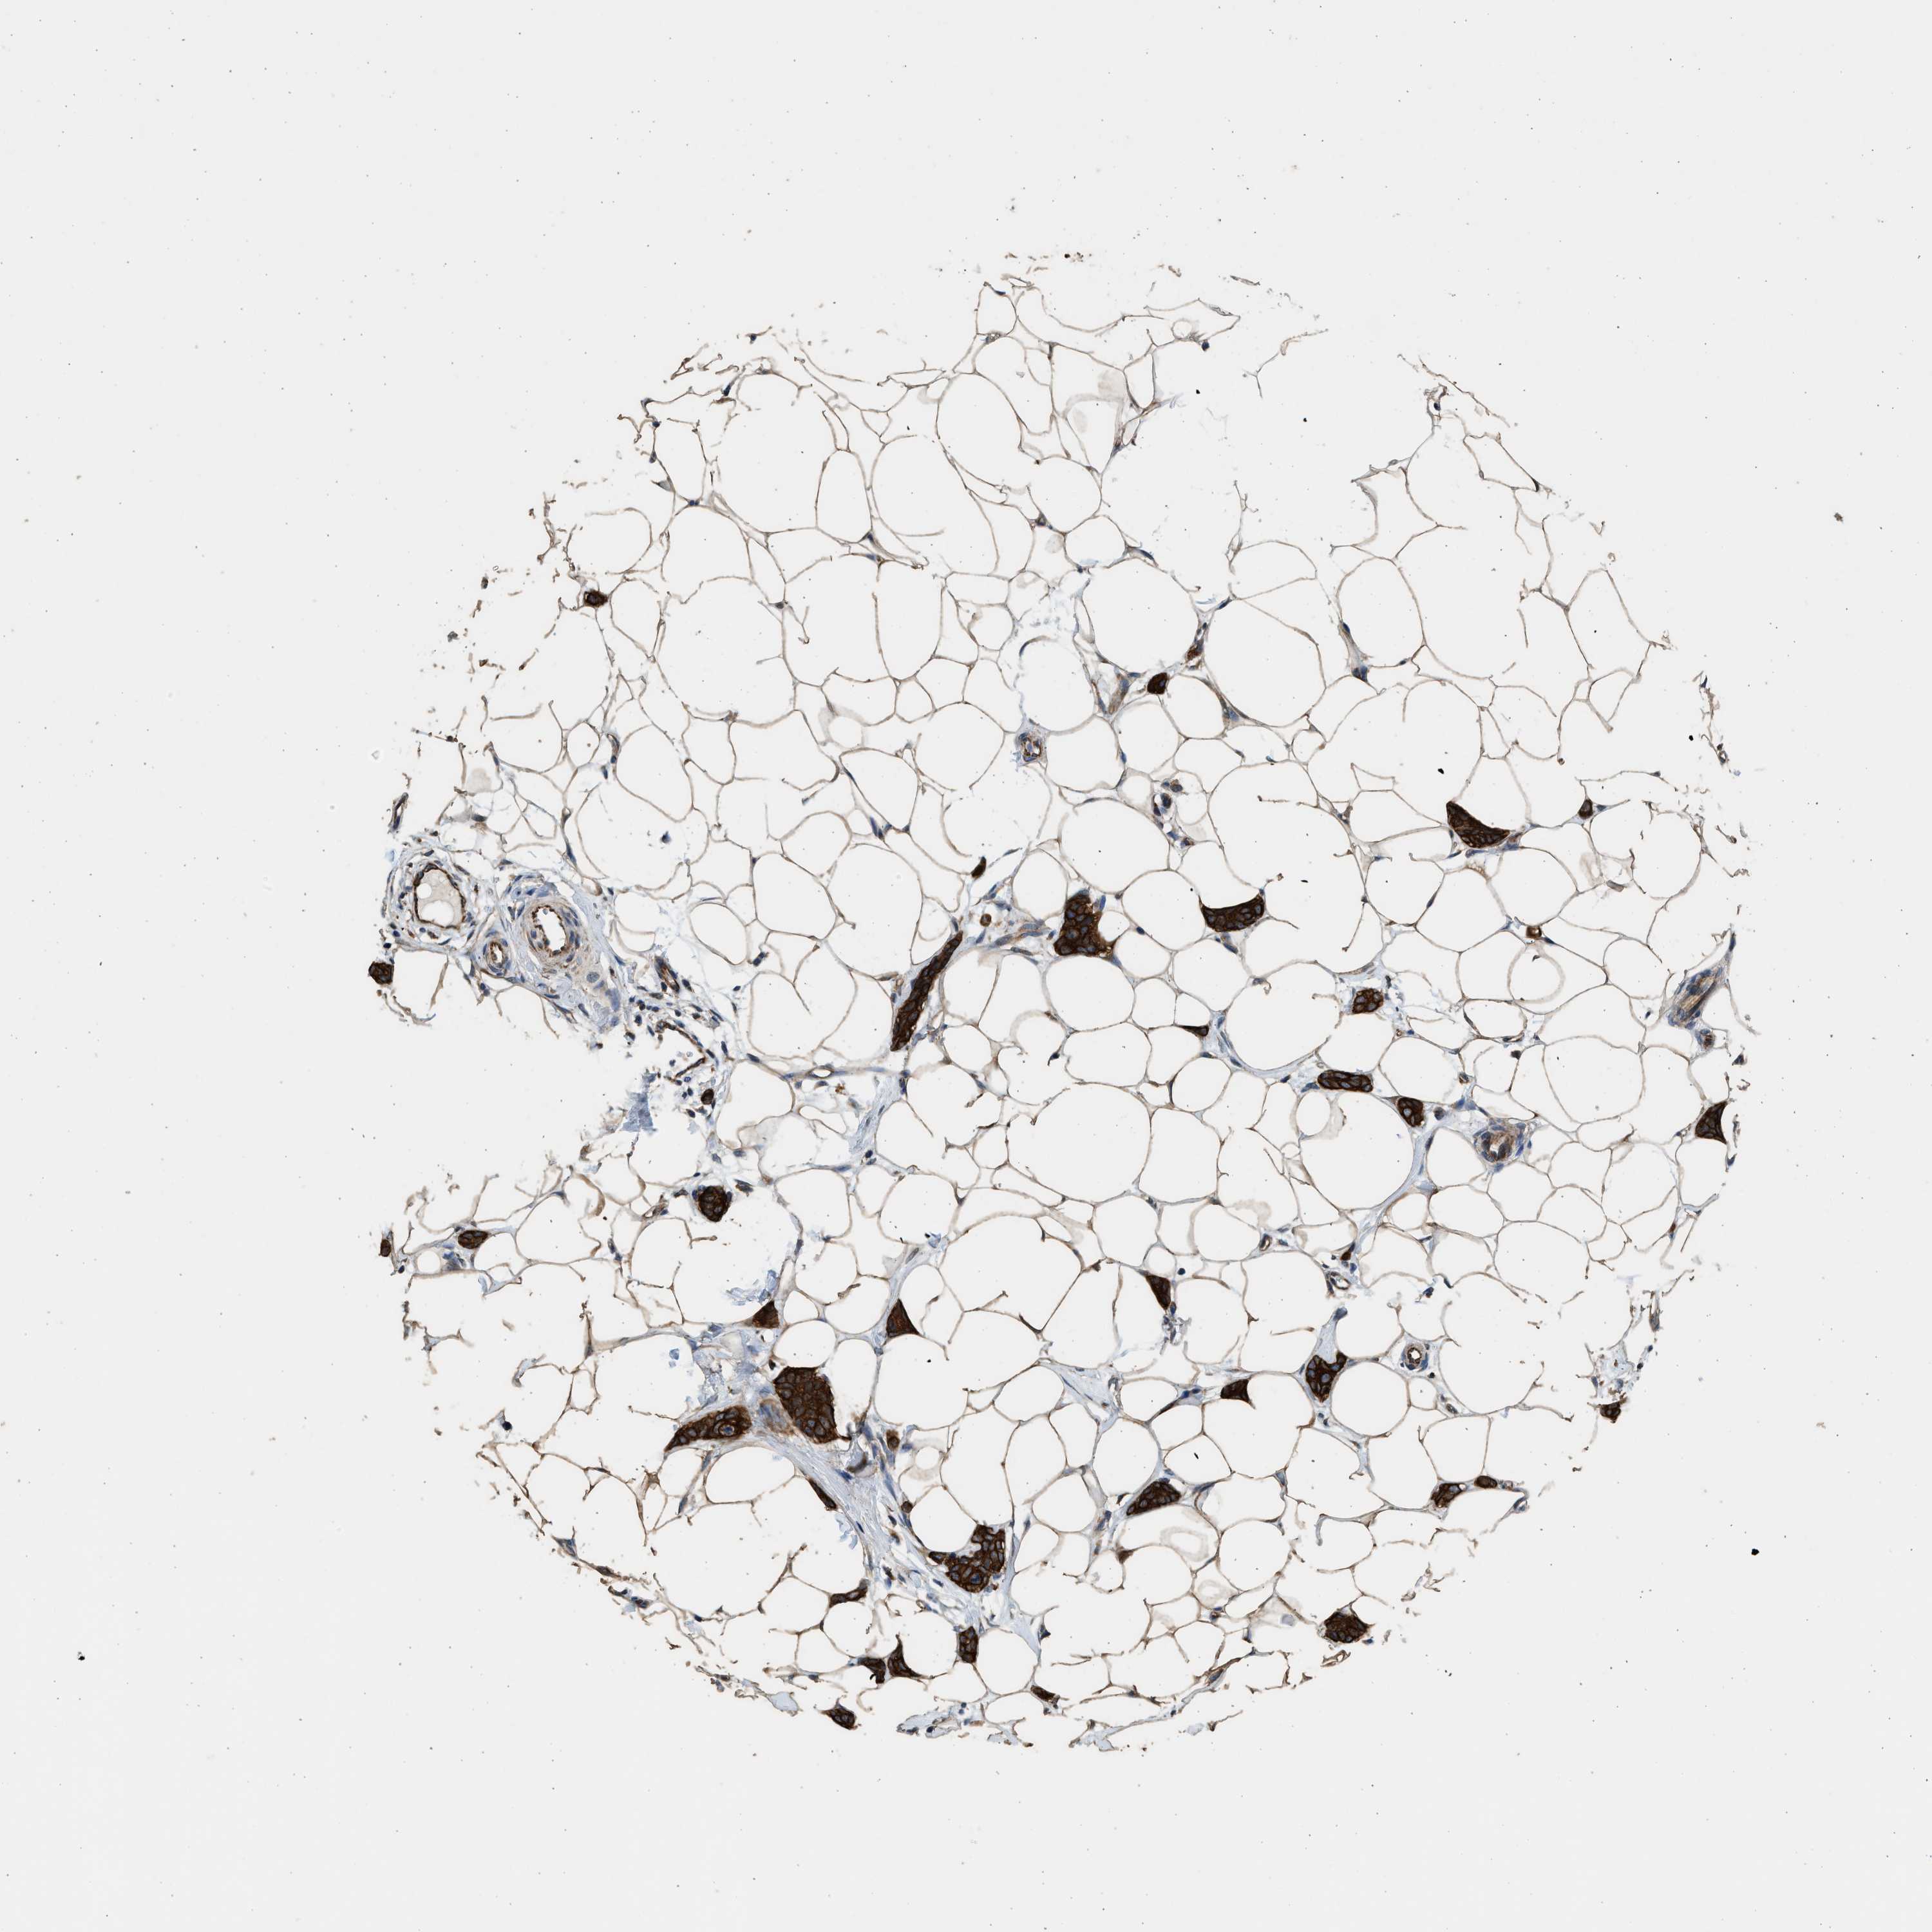

CANCER BREAST CANCER Show tissue menu

BRCA TCGA BRCA VALIDATION PROTEIN EXPRESSION